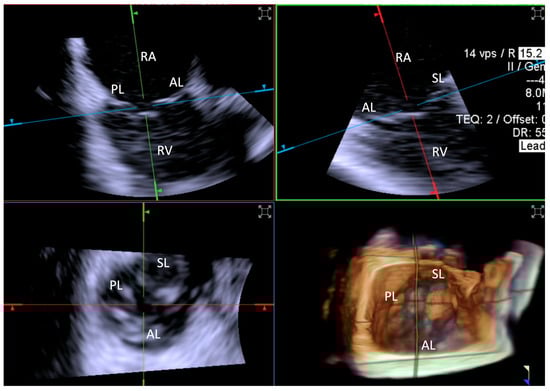

- Step number 5: clocking.

- Step number 6: grasping.